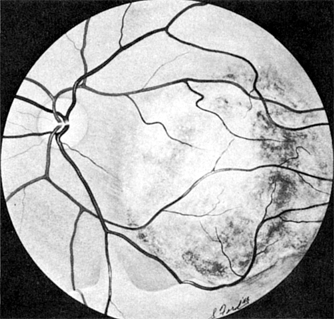

Nevi (Figures 7-7 and 7-8) are usually flat lesions with or without pigment lying in the stroma of the tissue. On the anterior surface of the iris, they may be noted as iris "freckles." Posteriorly in the choroid, one may see flat pigmented areas. Large choroidal nevi are difficult to differentiate from malignant melanomas. Their flat appearance and especially their lack of growth on repeat serial examinations are important in the differential diagnosis from malignant melanoma.

Figure 7-7

Figure 7-7: Nevus of the iris. (Courtesy of A Rosenberg.)

Figure 7-8: Nevus of the choroid. (Photo by Diane Beeston.)

Because of the difficulties in differentiation from malignant melanomas, fundus photographs or careful line drawings should be made of all suspicious lesions. The elevation or thickness of these lesions can best be measured and documented by ultrasonography. Observations should be made periodically for changes.